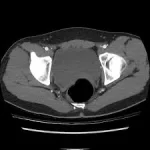

A CT Angiography Pelvis (Contrast-Enhanced Computed Tomography Angiography) is a specific imaging technique that provides detailed images of the blood vessels and blood flow in the pelvic region. This procedure is crucial for diagnosing vascular conditions, detecting blockages, and assessing injuries or abnormalities within the pelvic area. By using a contrast dye, the CT Angiography shows blood vessels, enables for more accurate view of the arteries and veins.

CT Angiography Pelvis is a non-surgical imaging procedure that creates detailed images of the blood vessels in the pelvic region. By using contrast dye, this scan improves the clarity of blood vessels, allowing healthcare professionals to identify conditions such as swelling, unusual blood vessel shapes, blockages, and injuries. The procedure is especially useful when regular scanning techniques like X-rays or MRIs do not provide enough information. Usually performed in a hospital or diagnostic center, the CT Angiography Pelvis report is generally available within a couple of days, helping with quick medical action.